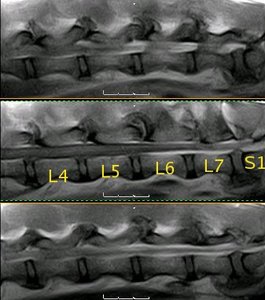

Resonancia magnética (SE T1 sagital) de la columna lumbar |

Resonancia magnética lumbo-sacra de pastor alemán |